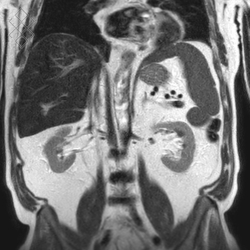

IRM Abdominale